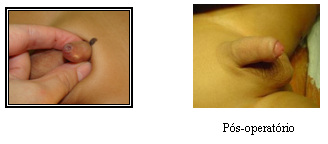

Para se tornar um Cirurgião Pediátrico, o médico precisa fazer dois anos de residência em Cirurgia Geral e mais três anos de residência em Cirurgia Pediátrica, onde verá as diferenças existentes no tratamento dispendidos a um adulto e a uma criança, ganhando habilidade no manuseio desses pacientes tão especiais. Normalmente as cirurgias são mais delicadas, realizadas sob anestesia geral e não necessitam de dormir no hospital (porém muitas delas podem ser realizadas em regime de Hospital Dia com internação que varia de 6 a 12 h). Casos cirúrgicos comuns em crianças são as hérnias inguinal e umbilical, cistos da região do pescoço como os branquiais e o tireoglosso, testículos que não estão situados na bolsa testicular, hipospádia e outras malformações do aparelho urinário, fimose, anquiloglossia (“língua presa”), tumores e doenças gastrointestinais.